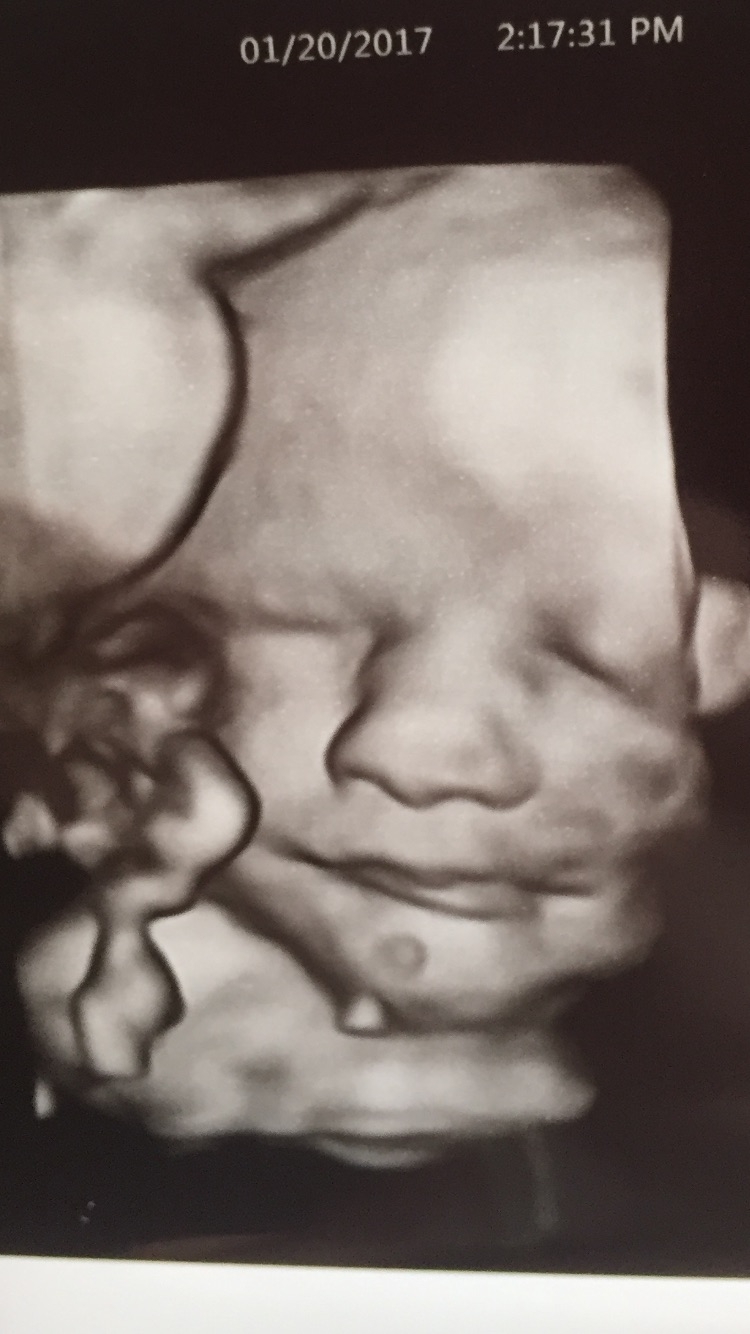

My little man at 31 weeks! Technology is so amazing.